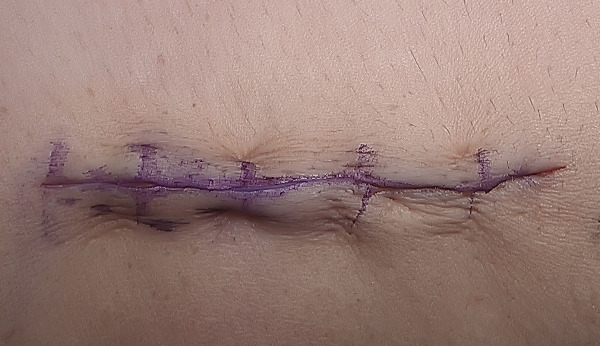

The skin is closed with a 3-0 monocryl suture in the subcutaneous layer, followed by a subcuticular 4-0 monocryl in the skin.

Steri-strips are applied to the wound, which is infiltrated with several cc’s of local anesthetic. A dry sterile dressing is then applied, and the arm is placed into a postop-hinged elbow brace locked at 90° of flexion and neutral forearm rotation. The patient is awakened and the tourniquet is released following dressing application.